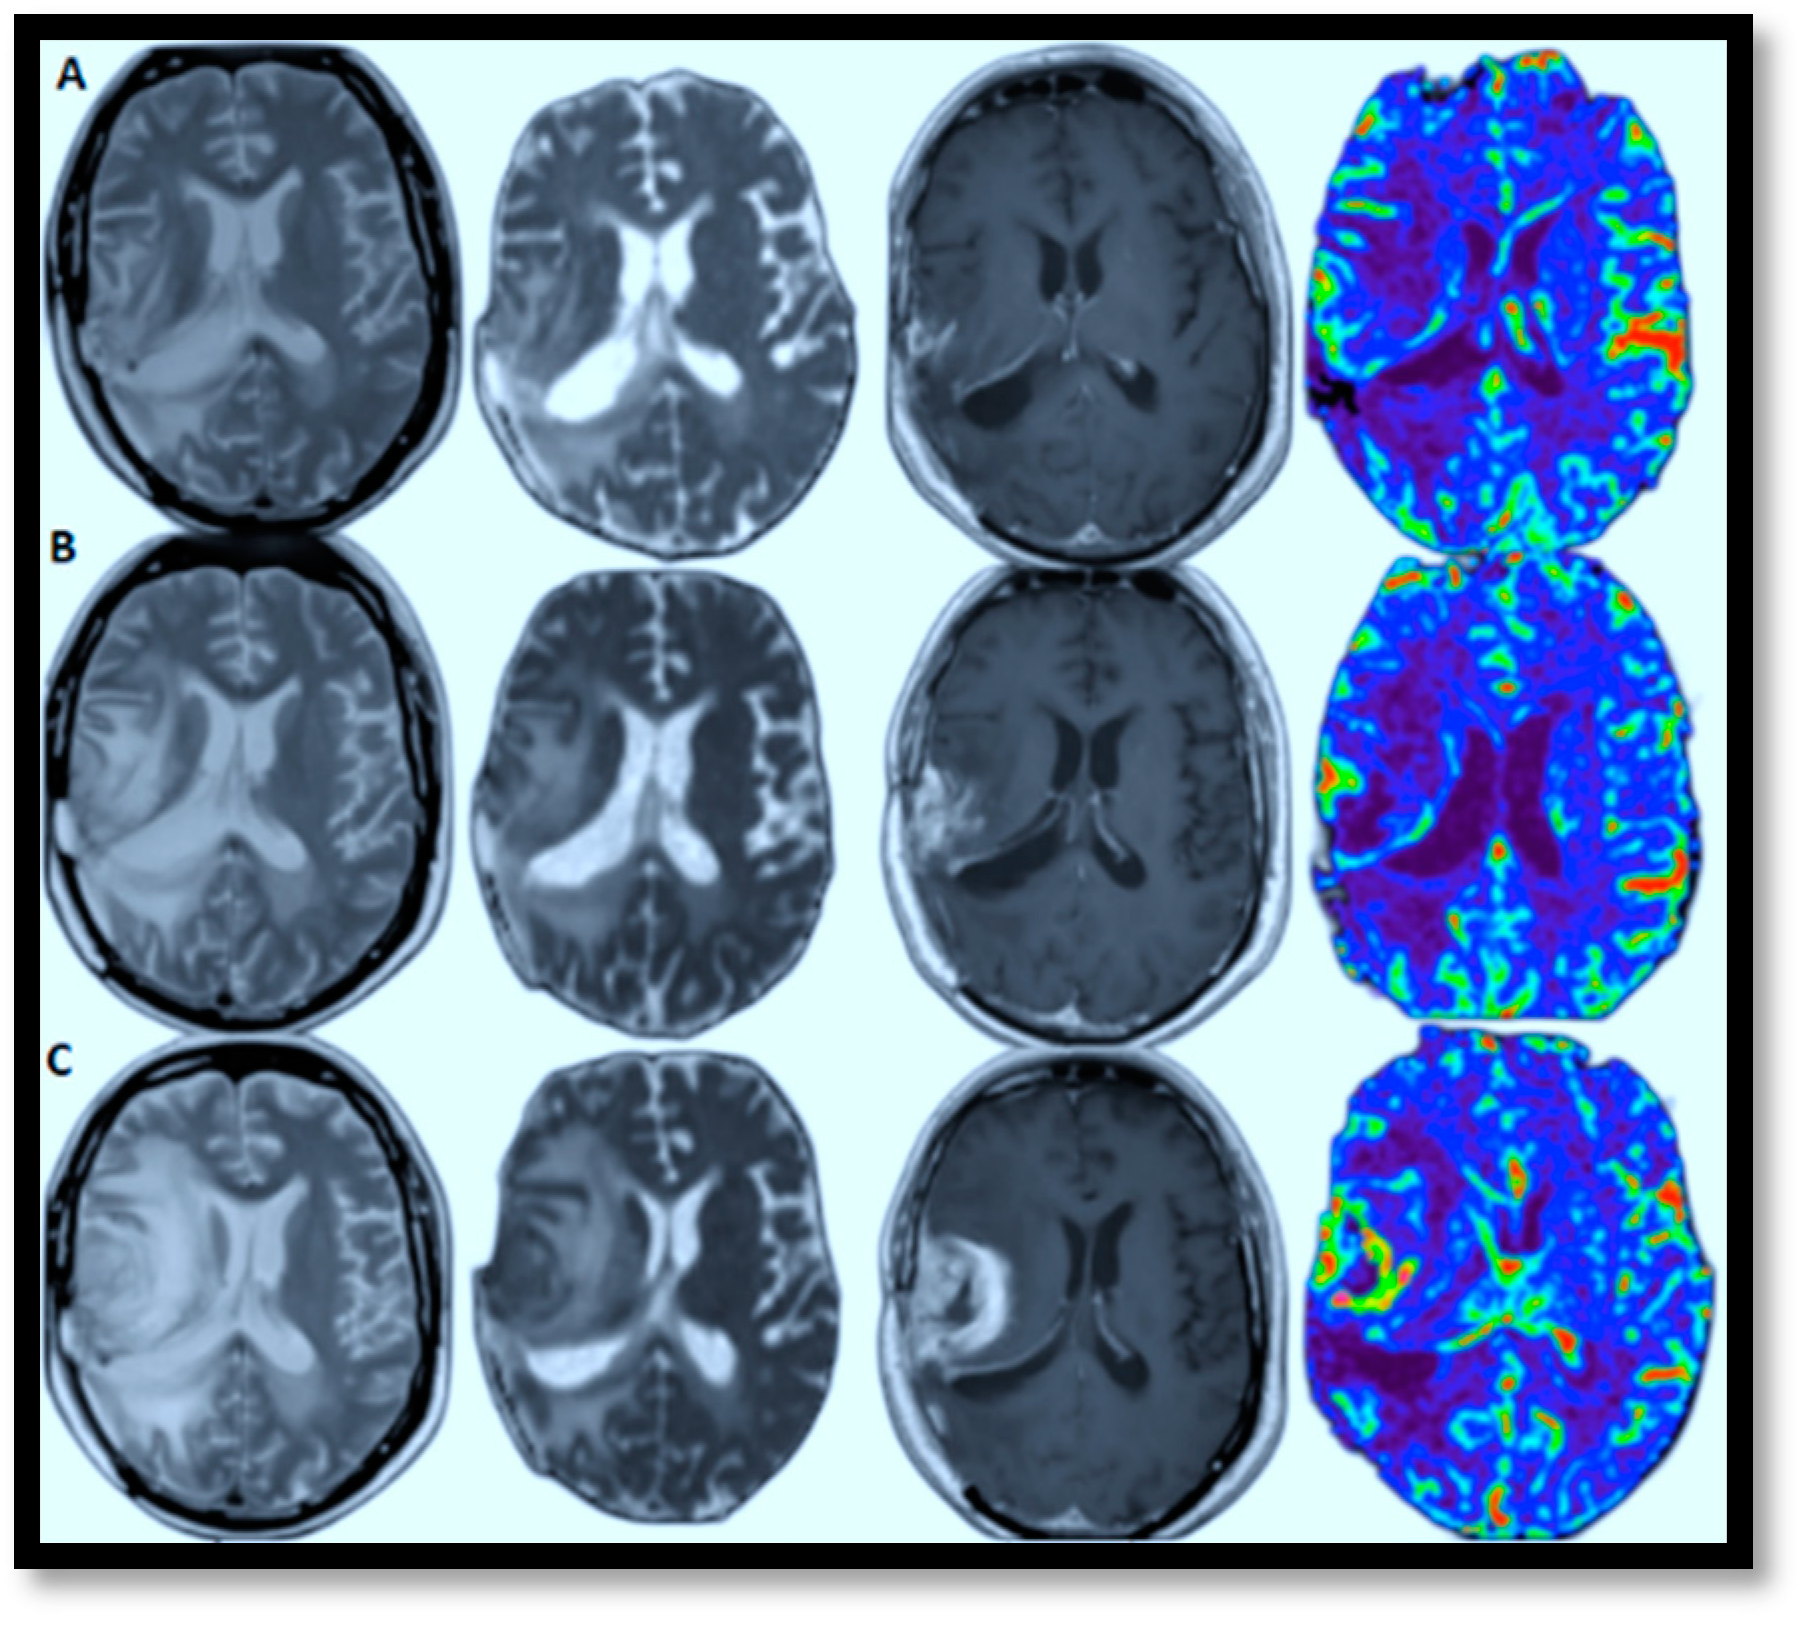

4.3. Brain MRI Tumor Progression Models

AI-powered predictive analytics enables proactive and personalized interventions by forecasting disease progression. In brain MRI brain tumor progression modeling, AI methods excel because they can identify complex patterns and relationships within high-dimensional data. These approaches effectively process large datasets, capture non-linear relationships, and learn features directly from raw data, which is crucial for medical imaging. View-specific brain MRI models exemplify this, demonstrating automated feature extraction with reliable accuracy and scalable architecture. This facilitates personalized medicine by identifying critical regions driving disease progression. Figure 7A–C illustrates this by showcasing glioblastoma progression through (T2, ADC map, T1-enhanced, and CBV) MRI scans taken at the 2nd, 4t, and 6th months, highlighting relapses and guiding the development of tailored treatment plans [70]. The color in the rightmost image signifies the volume of blood in a given amount of brain tissue. Below, a few specific models are discussed that have successfully tried to model brain MRI tumor progression with reasonable accuracy.